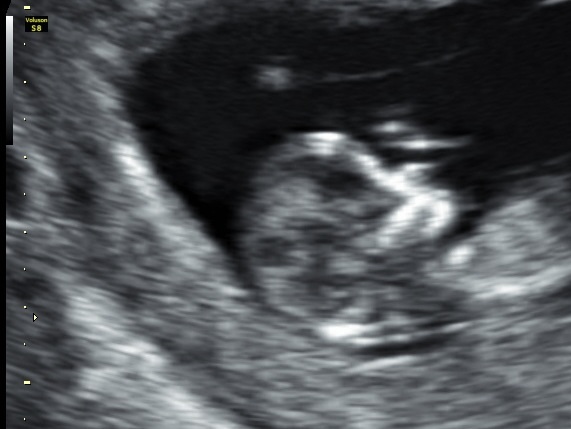

Hi,just wondering what's the best shot, girl or boy?

Can't see the nub, outside of the shot.

Based on skull theory i would say boy